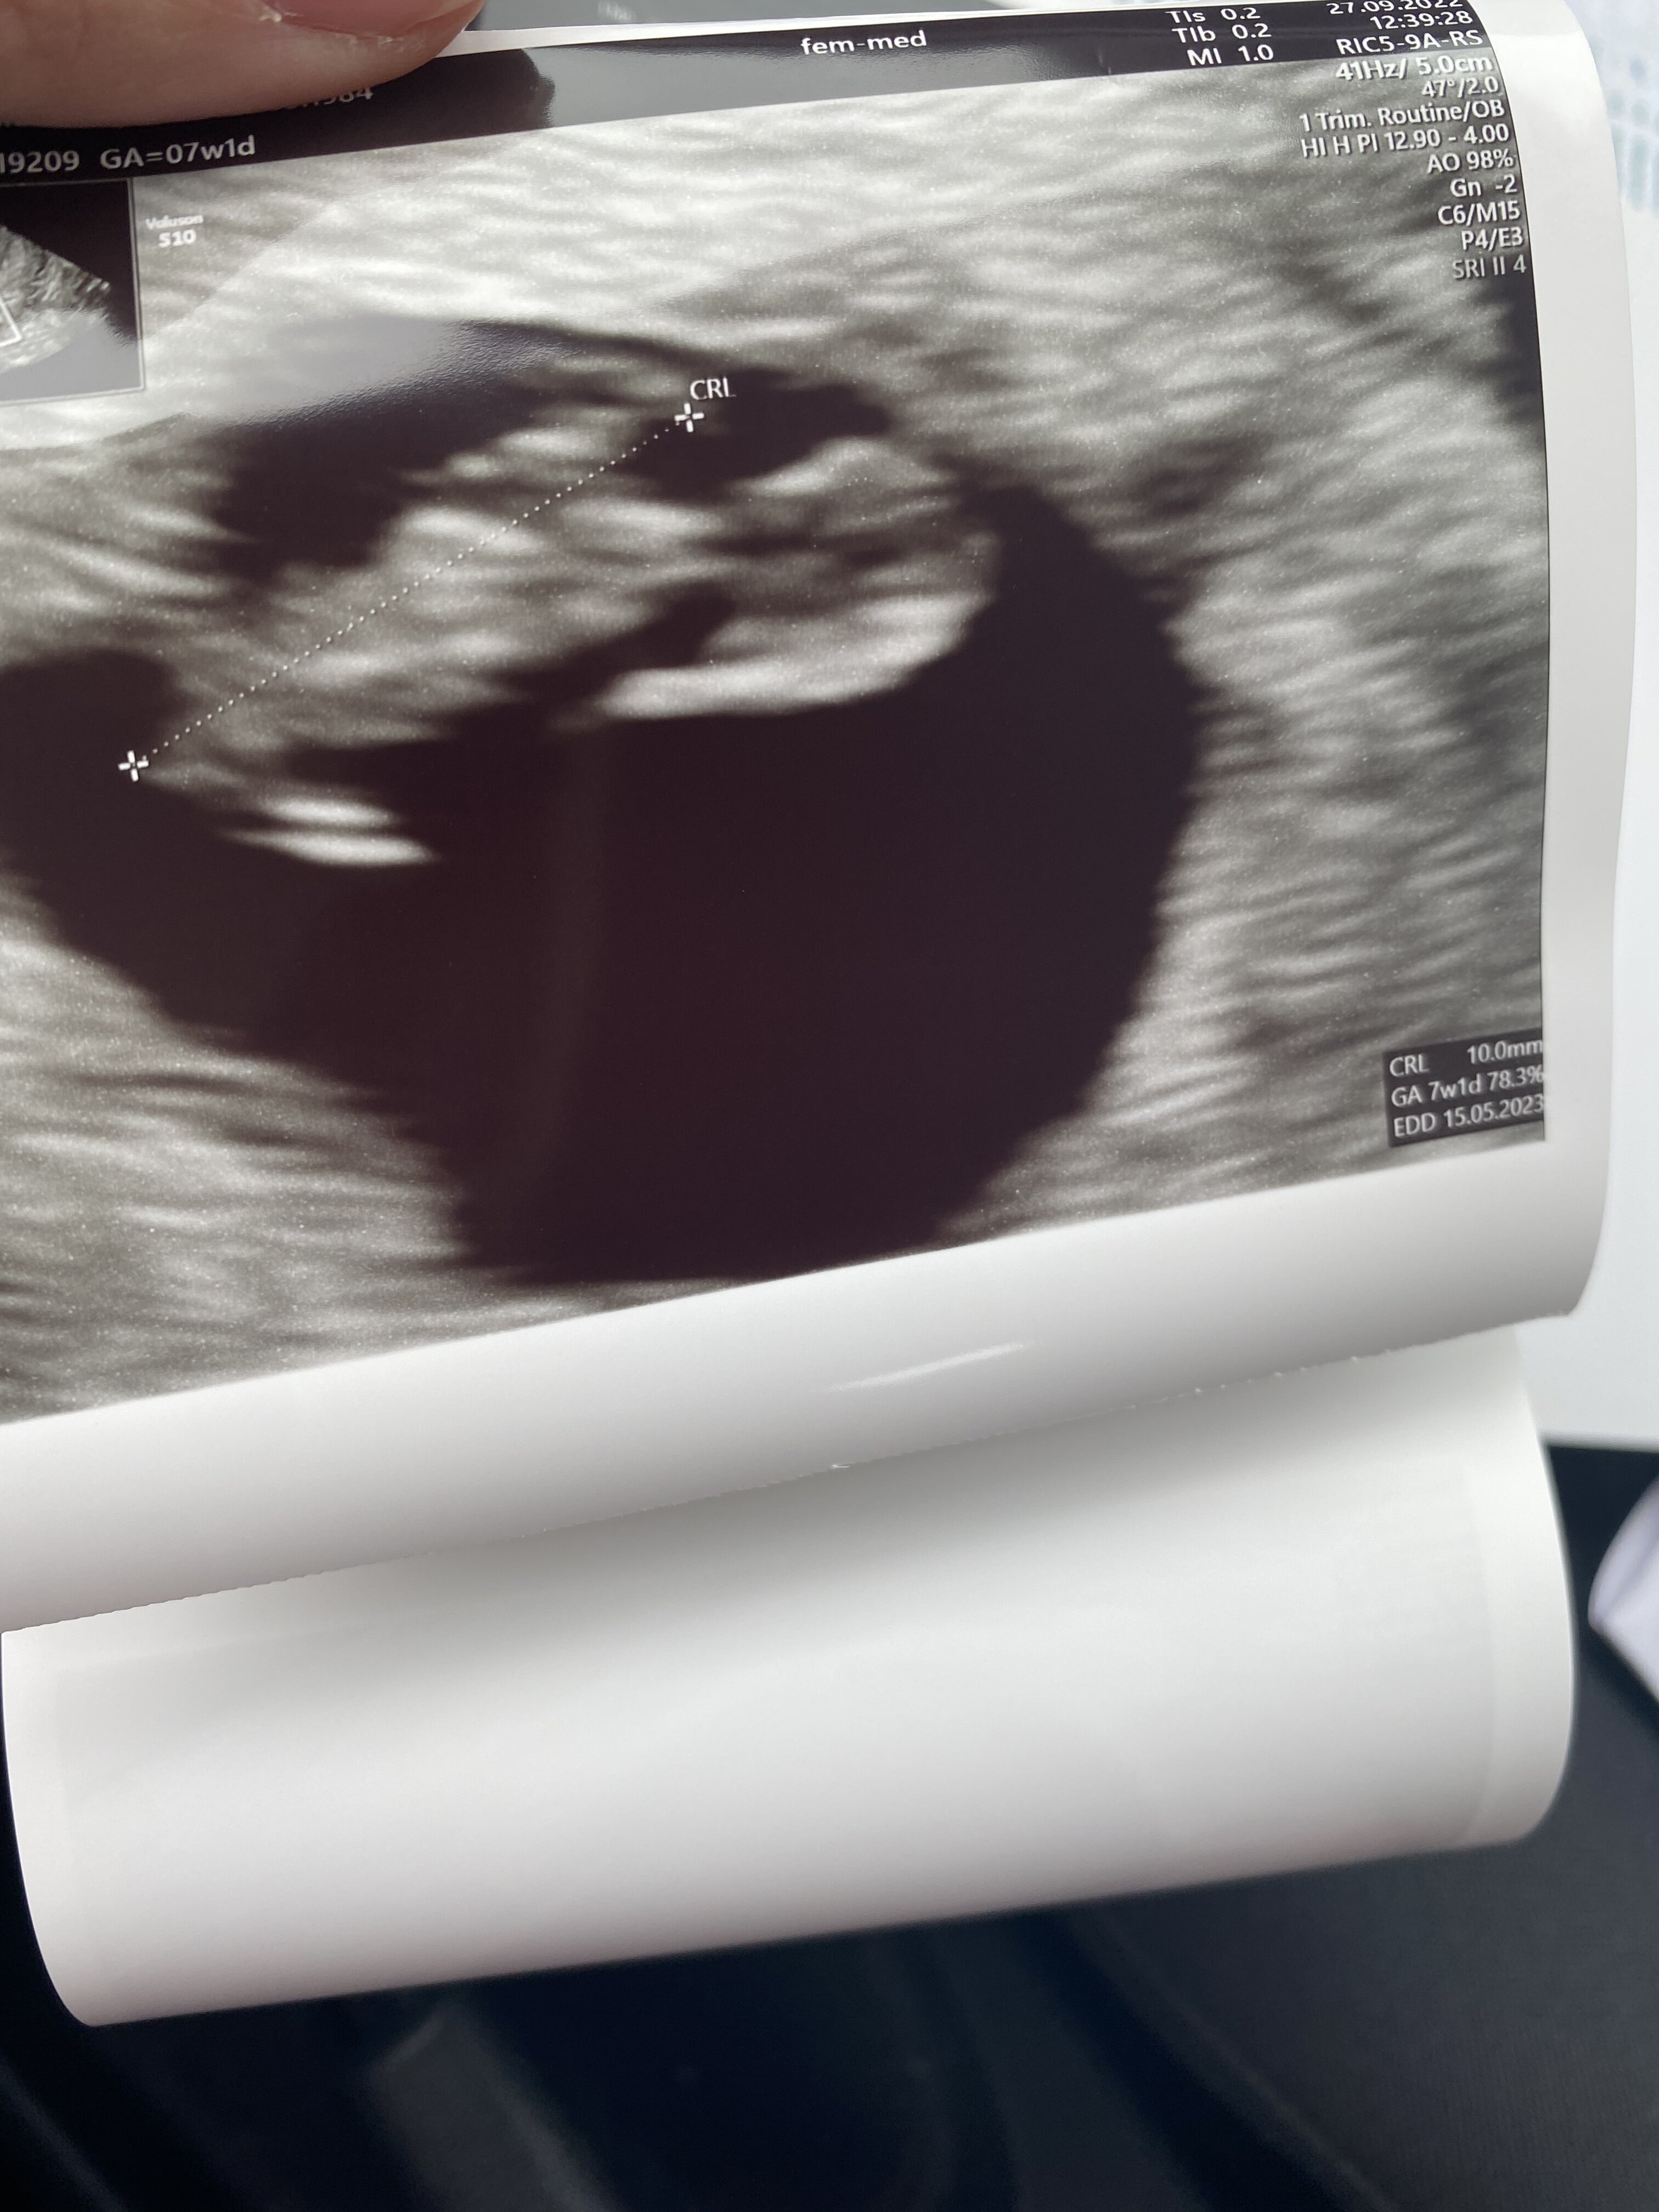

Z Kropkiem wszystko ok. Ma już cały 1 cm

bije mu serduszko. I wiek z om pokrywa się idealnie z wiekiem ciąży.